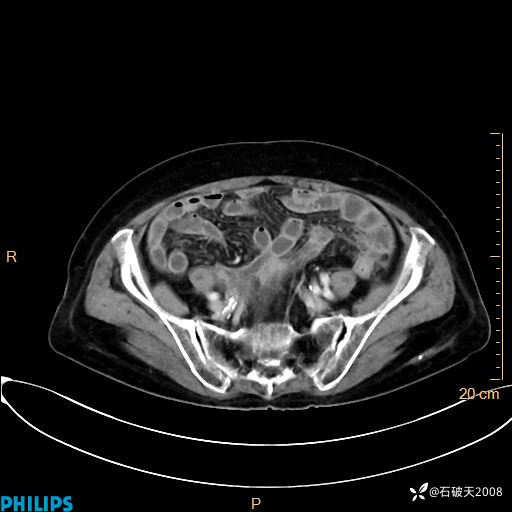

平扫